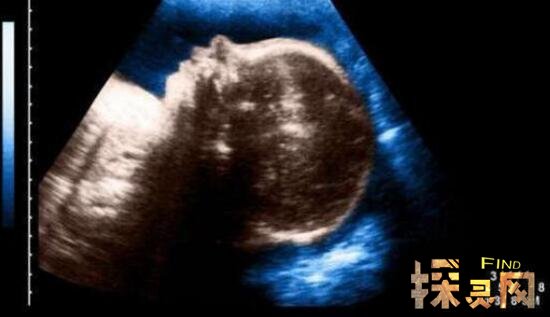

虽然这种畸形的发生不算罕见,但是通过孕期的超声检查,有86%的病例是能够被查处。曾有报道,南京的唐女士因长期受新车内超标甲醛的影响,在孕期第三个月进行超声检查时,竟然查出胎儿存在畸形问题,不得不引产,结果真的引产出一个已死亡的一只眼的婴儿。